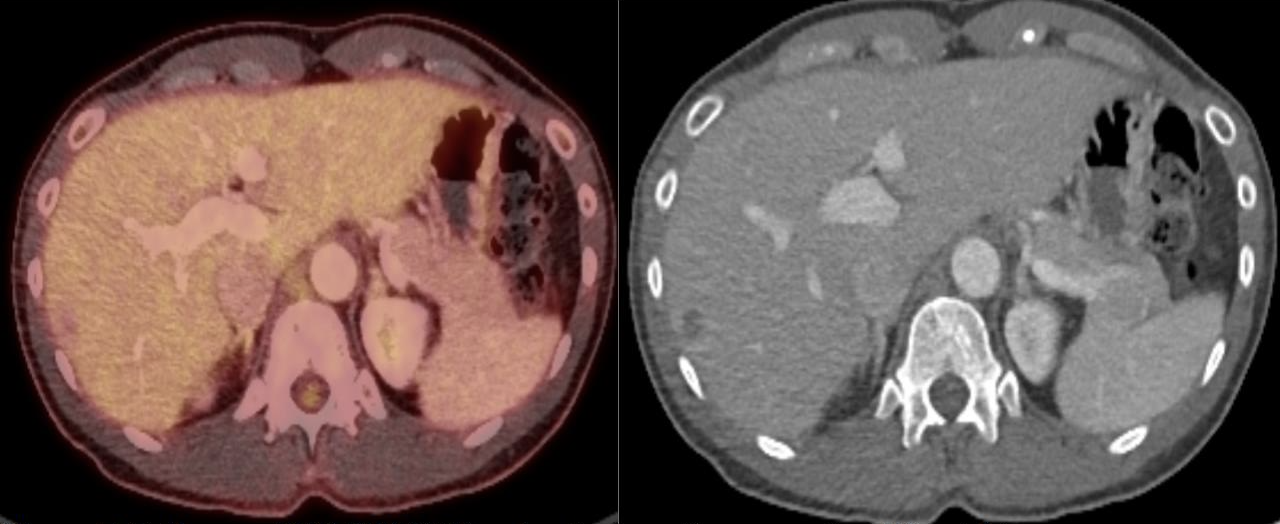

The patient was positioned prone oblique on the CT table (Figure 2). The procedure was performed under general anesthesia given the prone positioning, required precision for needle placement, and anticipated length of cryoablation. Under CT guidance, an 11-gauge bone access needle was advanced via a left transpedicular approach across the T12 vertebral body. Coaxial technique through this access was used to obtain both fine needle aspiration (FNA) and core biopsy samples (Figures 3-4). Immediate pathology assessment of the FNA samples confirmed metastatic adenocarcinoma. A single Endocare 17R cryoablation probe (Varian) was advanced through the 11-gauge access needle into the center of the nodal metastasis. Cryoablation was performed for 3 freeze-thaw cycles with intermittent CT monitoring to ensure adequate coverage of the lymph node and to minimize injury to the adjacent normal structures (Figures 5-6). All needles were removed, and the patient was extubated. After an uneventful overnight recovery, the patient was discharged home the following day.

FIGURE 3. Intraprocedure axial noncontrast CT image shows 11-gauge bone access needle with a 22-gauge Chiba needle inserted coaxially for fine needle aspiration. A white circle marks the target retrocrural lymph node.

FIGURE 4. Intraprocedure axial noncontrast CT image shows an 18-gauge core needle biopsy device passed through the 11-gauge bone access needle, with sampling trough positioned across the target retrocrural lymph node.

FIGURE 7. Follow-up FDG PET/CT fused and attenuation correction CT axial images demonstrated no residual FDG activity at the site of treated metastasis. Linear sclerosis is noted along the bone needle trajectory, consistent with osseous healing.